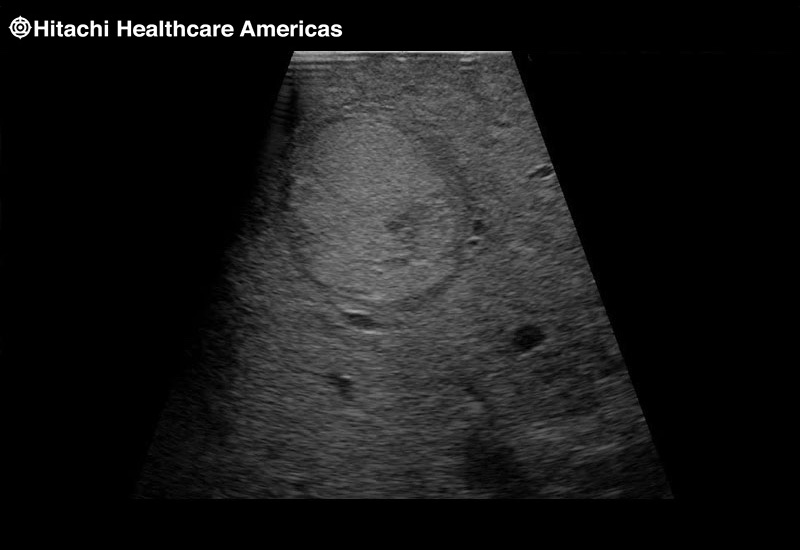

Superior guidance for all applications

Fujifilm Healthcare Americas is committed to designing tools that help surgeons navigate inside the human body and provide the necessary information to immediately make critical surgical decisions.

Fujifilm Healthcare's dedication to Surgeons provides outstanding ultrasound technology, professional support and the specialized tools necessary to best perform comprehensive real-time ultrasound imaging in Breast Surgery, General Surgery, Laparoscopic Surgery, Neurosurgery, Robotic Surgery and Surgical Oncology.

Fujifilm Healthcare’s ARIETTA Precision features state-of-the-art digital architecture and advanced imaging technologies to redefine the capabilities of surgical ultrasound.

Fujifilm Healthcare’s ARIETTA Precision features state-of-the-art digital architecture and advanced imaging technologies to redefine the capabilities of surgical ultrasound.